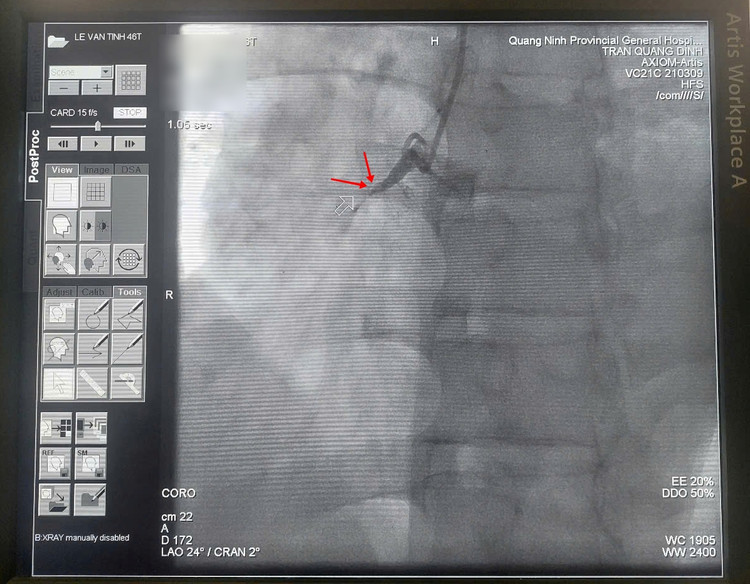

Kết quả chụp mạch cho thấy 3 thân động mạch vành tổn thương nặng, huyết khối làm tắc cấp tính hoàn toàn động mạch vành phải, động mạch mũ và động mạch liên thất trước hẹp nặng.

| Hình ảnh động mạch mũ (trái) và động mạch liên thất trước (phải) hẹp nặng. |